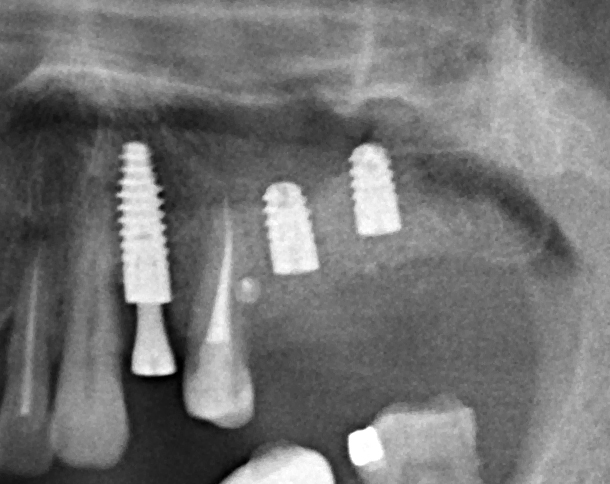

В прошлый раз мы с вами говорили о сочетании имплантации и остеопластики методом аутотрансплантации крупных костных фрагментов. Сегодня мы продолжим тему и поговорим о сочетании имплантации и остеопластики методом направленной костной регенераци (НКР), что встречается гораздо более часто и, на первый взгляд, выглядит более естественно. Вот ситуация до операции:

во время операции (плюс снимок по завершении):

Вернемся к нашему клиническому случаю. Мы уже поставили импланты с расчетом на будущую высоту альвеолярного гребня и положение будущих зубов:

Вот снимок сразу после операции: